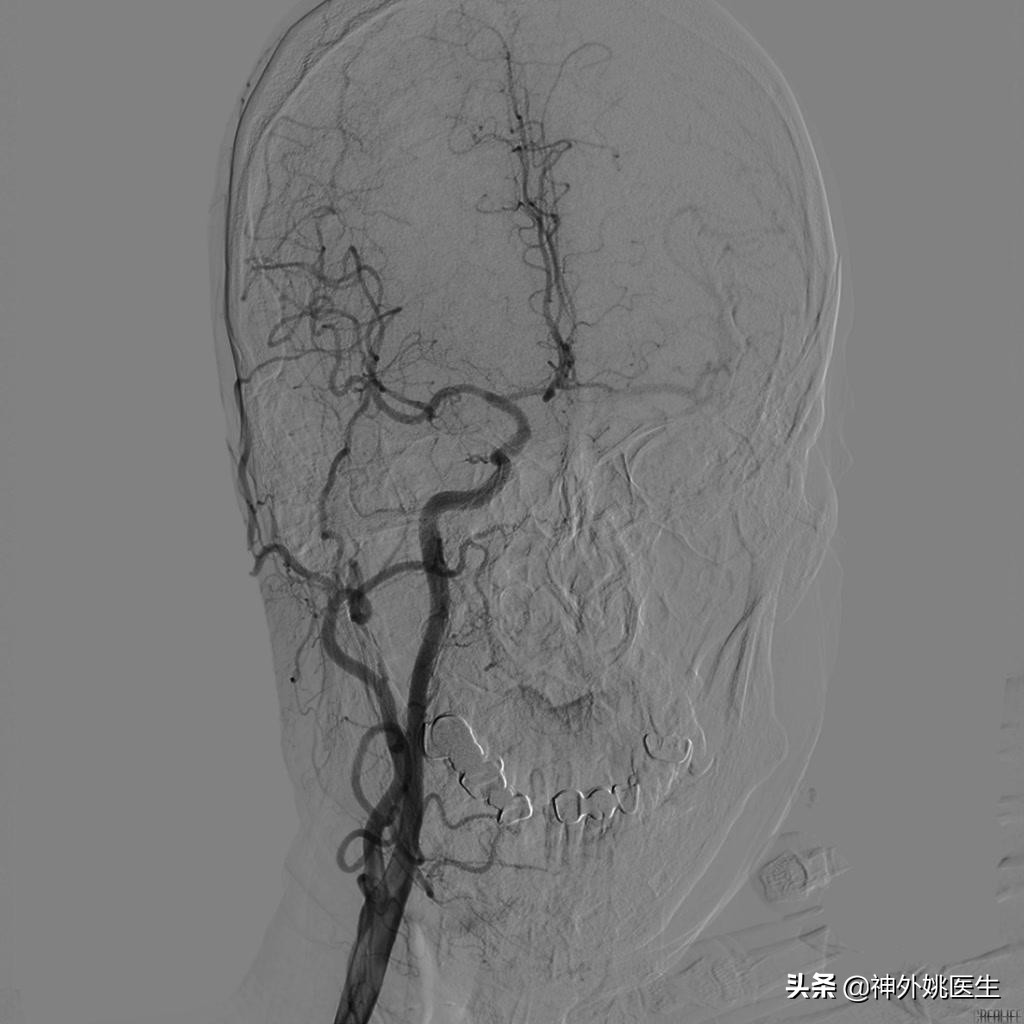

术前DSA检查:(图3-6)

图5 左侧颈动脉造影示左侧大脑前动脉显影欠佳。

图6 椎基底动脉造影示左侧后交通动脉开放,左侧大脑中动脉显影。